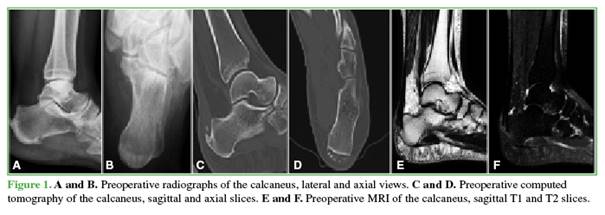

The retrocalcaneal bursa is resected, the diseased portion of the tendon is debrided, and Haglund’s deformity is resected using an oscillating saw (Figure 1). The healthy remnant of the Achilles tendon is then reinserted at the insertion site using the Achilles SpeedBridge™ double-row suture system. Finally, layered closure is performed (Figures 2 and 3).

Post-surgical Protocol